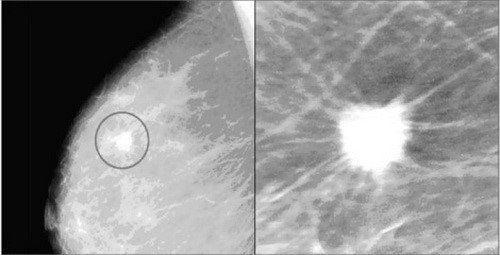

Vôi hóa lành tính được nhận định trên phim chụp X-quang điển hình là tròn, to và thô với bờ nhẵn, dễ nhận ra hơn vôi hóa ác tính. Vôi hóa liên quan đến u ác tính (cũng như nhiều loại vôi hóa lành tính) thường rất nhỏ và cần sử dụng kính phóng đại để nhìn thấy rõ hơn.

• Vi vôi hóa hay các nốt vôi hóa nhỏ có kích thước rất nhỏ, xuất hiện với nhiều đốm trắng nhỏ trên nhũ ảnh. Tuy nhiên, nếu chúng xuất hiện thành chùm hoặc không có giới hạn nhất định, các nốt vôi hóa nhỏ có thể là dấu hiệu của bệnh ung thư, cần phải được kiểm tra đầy đủ và chẩn đoán xác định bởi bác sĩ chuyên khoa.